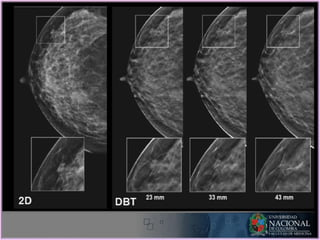

• FDA : 2011 como adyuvante a la

mamografía

• Principio de la tomografía lineal

• Uso en senos densos reduce falsos

negativos

• Incremento en la dosis de radiación

• Mayor tiempo de estudio

• FDA :2011 como adyuvante a la mamografía • Principio de la tomografía lineal • Uso en senos densos reduce falsos negativos • Incremento en la dosis de radiación • Mayor tiempo de estudio NUEVAS TECNOLOGIAS: TOMOSÍNTESIS